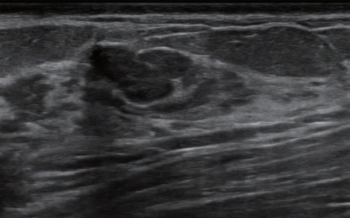

Researchers found that a deep convolutional neural network, incorporating B-mode ultrasound and shear wave elastography data, had nearly an 88 percent sensitivity rate for predicting neoadjuvant chemotherapy response in patients with breast cancer.

Emerging breast ultrasound research showed the use of computer-aided diagnosis (CAD), powered by deep learning, led to 24 percent and 36.9 percent improvements in accuracy and specificity, respectively, in the use of BI-RADS classifications by radiologists without breast ultrasound expertise.